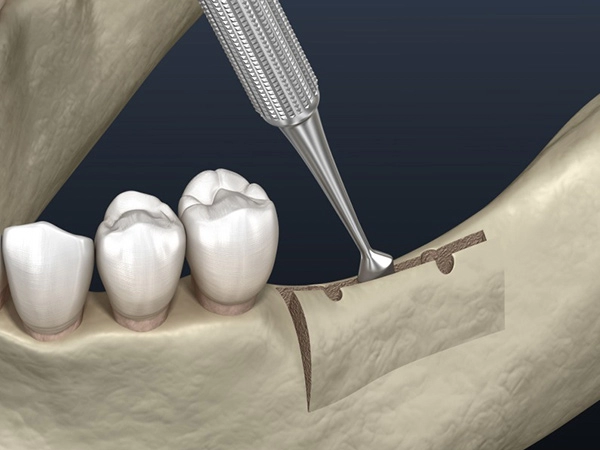

Такой вид операции по остеопластике, как расщепление альвеолярных отростков, проводят путём механического расширения стенок гребня и заполнения образовавшейся полости костным материалом. За счет этого компенсируется нехватка ширины кости. Выполняется одномоментно с установкой имплантатов. Метод применяется для нижней челюсти и на верхней для фронтальной зоны. При сильной вертикальной атрофии (нехватка высоты гребня) метод не применяется.

Такой вид операции по остеопластике, как расщепление альвеолярных отростков, проводят путём механического расширения стенок гребня и заполнения образовавшейся полости костным материалом. За счет этого компенсируется нехватка ширины кости. Выполняется одномоментно с установкой имплантатов. Метод применяется для нижней челюсти и на верхней для фронтальной зоны. При сильной вертикальной атрофии (нехватка высоты гребня) метод не применяется.